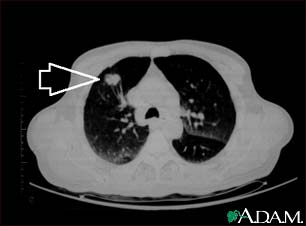

Lung mass, right upper lobe - CT scan

This is a CT scan of the upper lungs. This individual has a mass in upper part of the right lung (left side of picture).